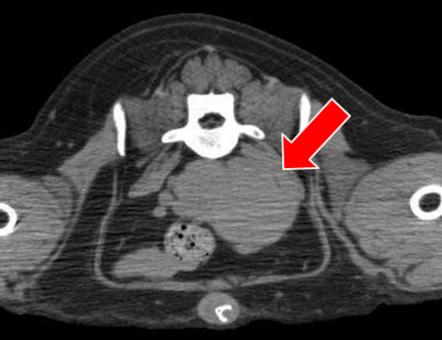

TAE後経過 ②

TAE後66日目 残存腫瘤の摘出手術

― 手術時のCT検査ではPR  ― 組織検査結果は胆管細胞腺腫

第225病日現在、再発なく全身状態良好

外科手術時(TAE後66日目)

TAE前